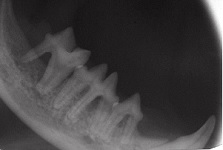

Radiography supernumerary tooth will have its own roots gemination will show double crown but not double the amount of roots (included radiogrph shows gemination of a mandibular 4th premolar tooth in a cat with 2 crowns and 3 roots instead of 1 crown and 2 roots).

Gemination Nov 2008-03